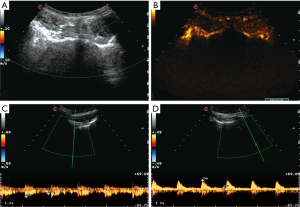

There were three result types of the CDUS and CEUS examinations: positive CDUS and CEUS, negative CDUS and CEUS, and negative CDUS but positive CEUS (Figure 1). After discontinuation of anti-TNF therapy, positive CEUS accounted for 61.5%; this was significantly more than positive CDUS (13.8%) (Table 2). The vascularization detected by CEUS for patients of relapse was significantly different from that of patients with remission (P<0.05). Between the time of withdrawal and relapse, the mean increase of the BASDAI, CRP, and ESR were 3.8 (±1.6), 14.6 mg/L (±21.2 mg/L), and 20.1 mm/h (±28.5 mm/h) respectively. All changes between the time of withdrawal and relapse were statistically significant. The changes in the BASDAI, CRP, and ESR correlated well with the positive CEUS results (P<0.05).

With the patient lying in the prone position, the probe was first oriented transversely at the sacral bone. It was inclined downward to identify the SIJ. The transducer was then turned counterclockwise to reveal the left SIJ and clockwise to reveal the right SIJ. We observed the blood flow in the area of the SIJ by CDUS after each SIJ was visualized. We selected the blood flow signal in the SIJ for the spectral measurement if the blood flow signal could be found both within and around the SIJ. If the arterial blood flow was detected, the resistive index (RI) was measured 3 times, reaching the mean value. Based on our previous research (25), we defined no blood flow, high RI of arterial blood flow (RI ≥0.7), the reversed phase in the diastolic phase or venous blood flow in the bilateral SIJs as negative CDUS; meanwhile, low RI of arterial blood flow (RI <0.7) in the unilateral or bilateral SIJs was defined as positive CDUS.

CEUS

First, a bolus of 1.2 mL agent (SonoVue®) was injected intravenously, and the pipe was immediately washed with 5 mL saline water. At the same time, we started the contrast-enhanced mode for timing and observed the process of blood perfusion in both SIJs continuously and dynamically. After developing of the SIJ, color Doppler and spectral Doppler were used to measure RI. The definitions of positive CEUS and negative CEUS were the same as above.